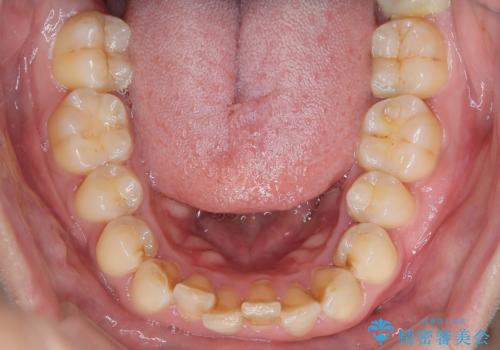

- 下の歯のがたつきを主訴に来院されました。

下の歯のがたつきと右の奥歯の噛みあわせ改善するために治療計画を立てることにしました。

下の前歯のがたつき改善にはIPR(歯と歯の間を削る処置)を行いました。